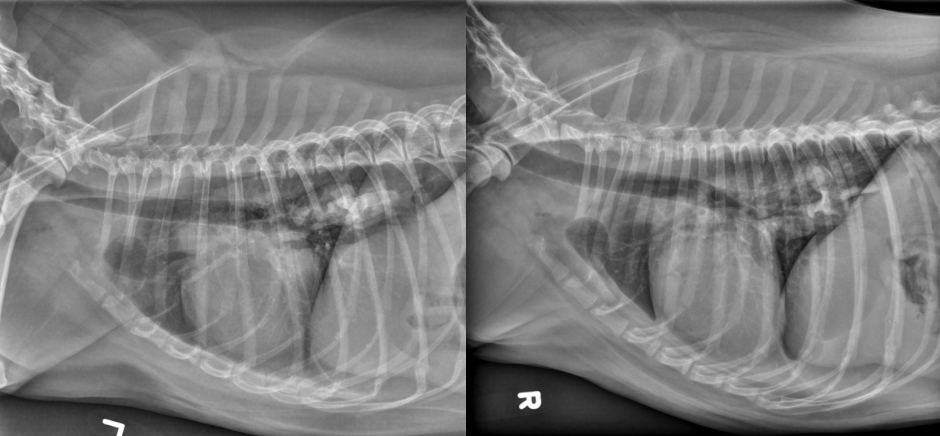

● 7 yo castrated male Golden

Retriever

● Lethargy for last 24h

fat along cranioventral aspect of thorax, maybe fluid too at heart apex.

pericardial effusion: very round heart margin tells you its fluid and not just cardiomegaly.

mild bronchial pattern